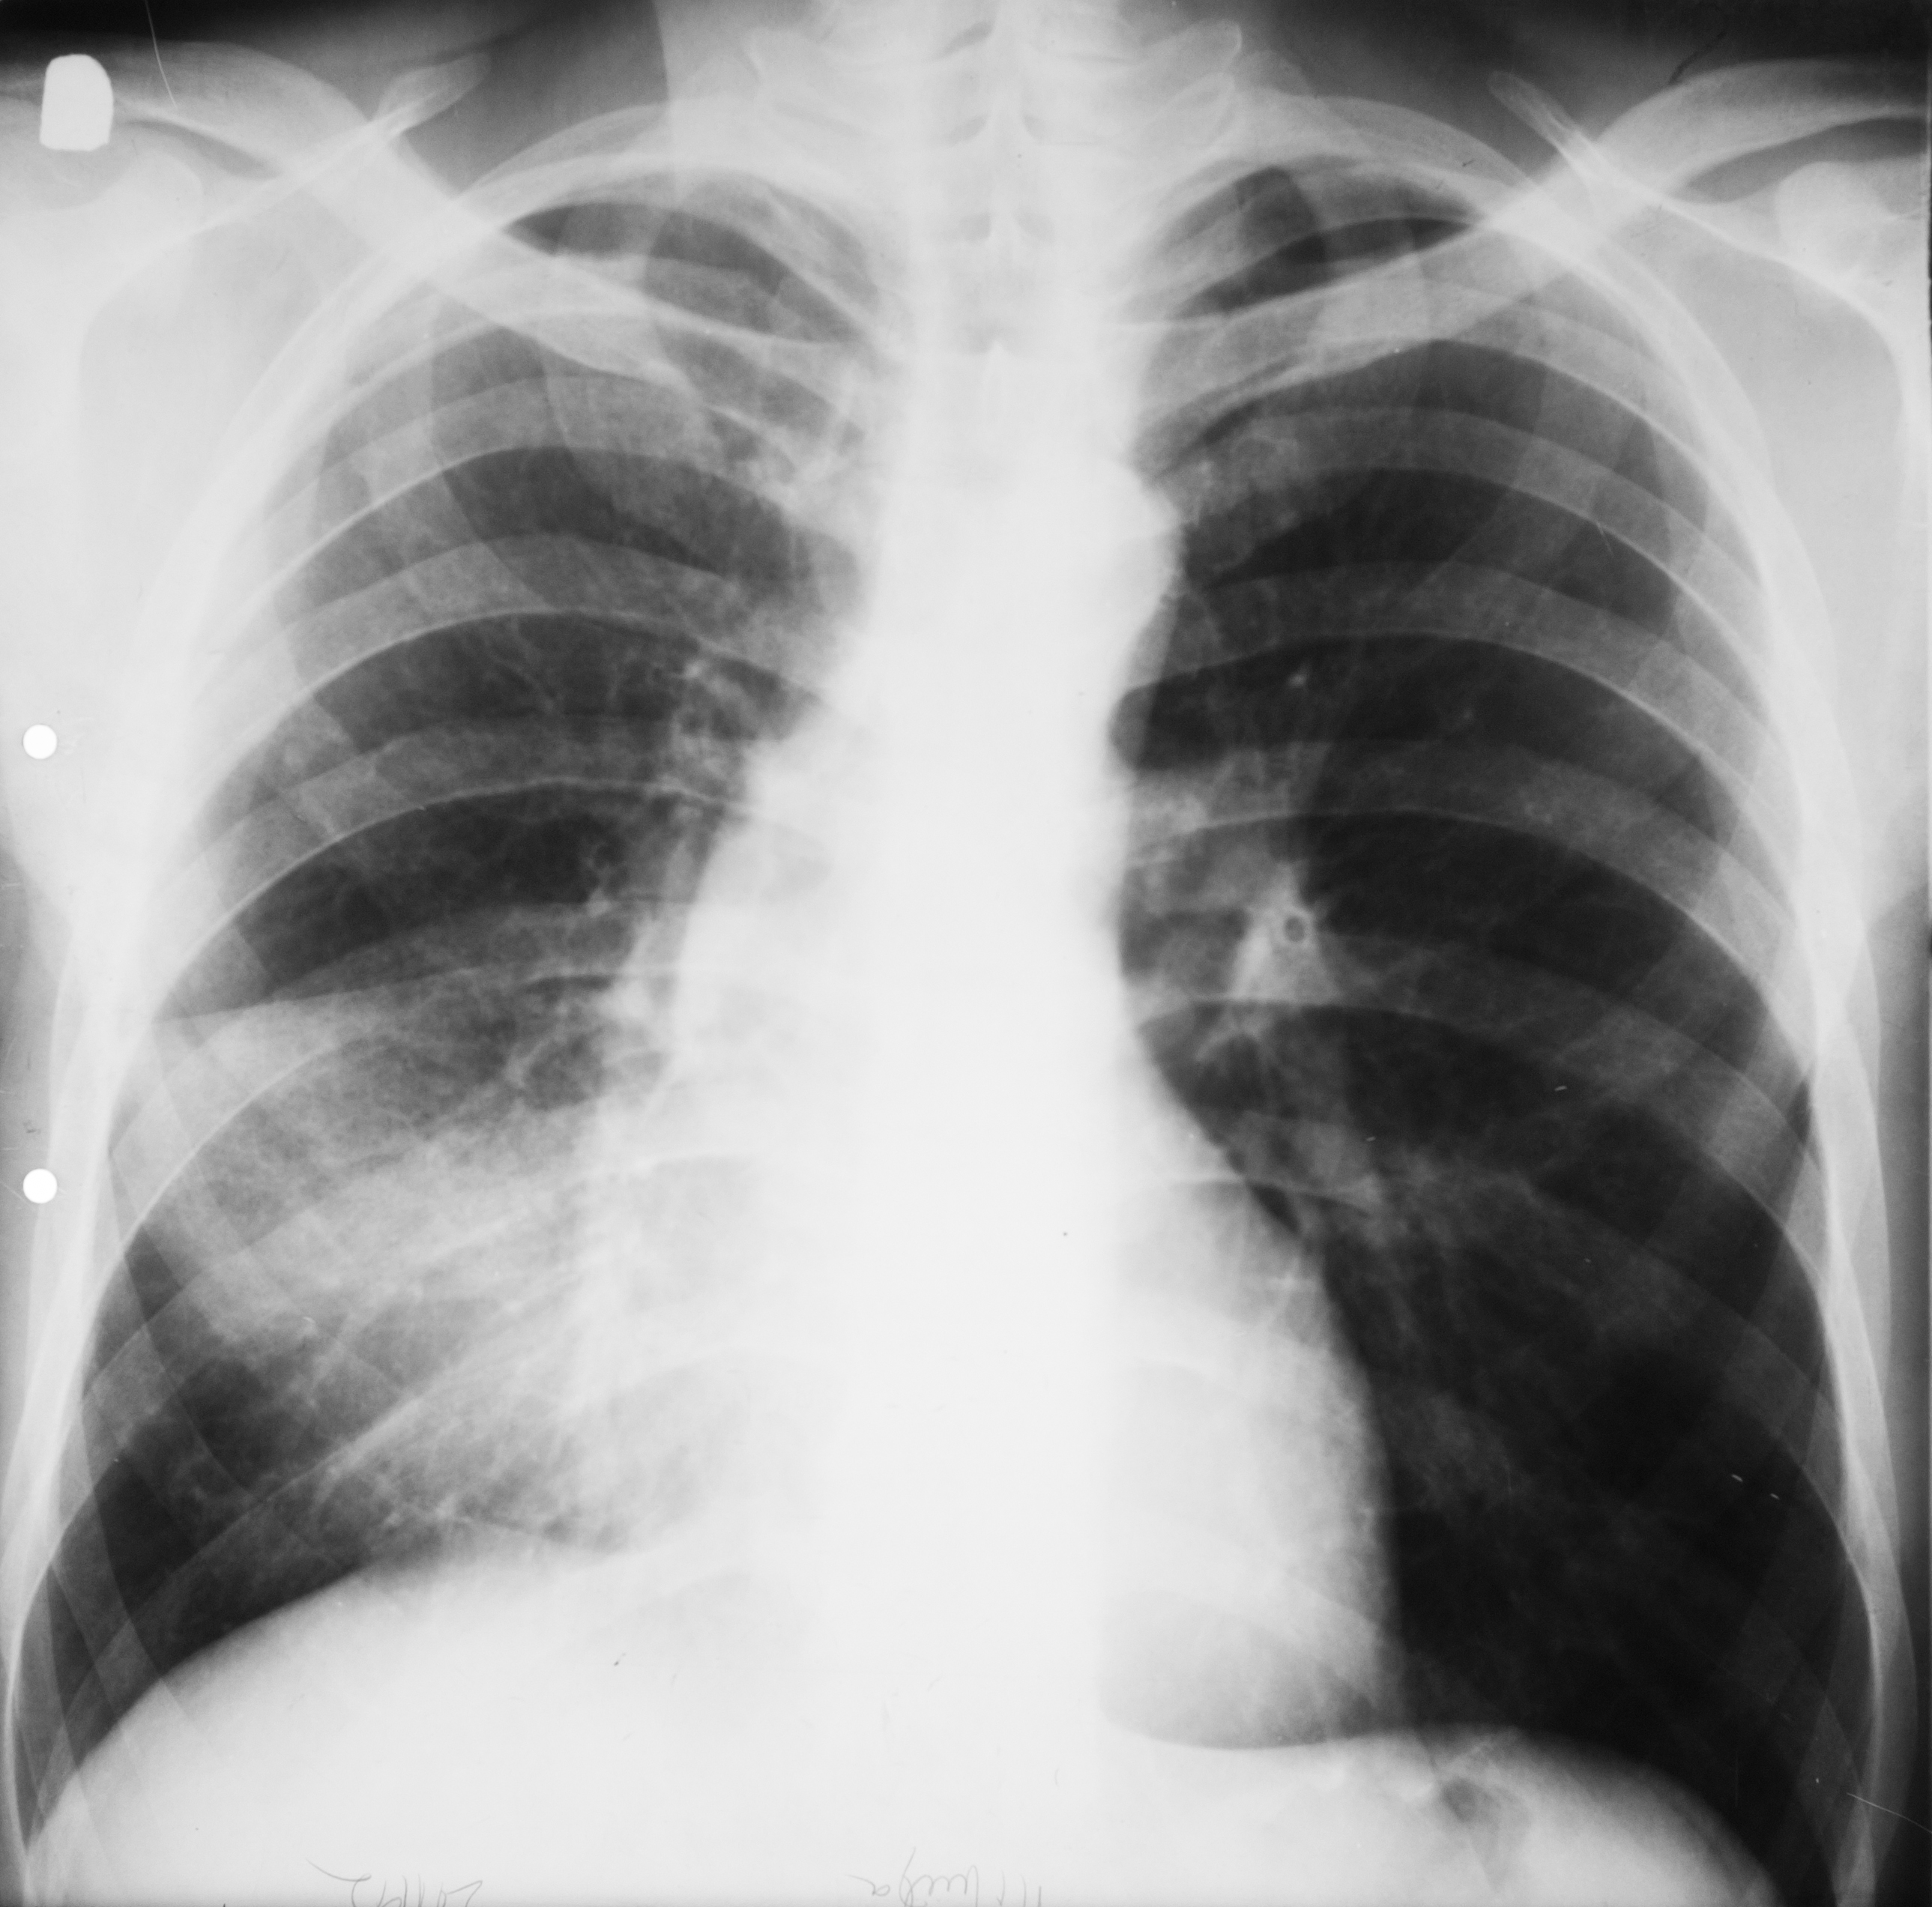

Rx toraco-mediastino-pleuro-pulmonară – opacitate pulmonară în treimea mijlocie a câmpului pulmonar drept,net liniar delimitată inferior, ........... delimitată superior,cu bronho-gramă aerică,cel mai probabil pneumonie

PNEUMONIE FRANCĂ LOBARĂ

Proces de condensare în jumătatea inferioară a câmpului pulmonar drept cu bronhogramă aerică ce vine în contact cu cordul

PNEUMONIE FRANCĂ LOBARĂ

Condensare cu bronhogramă aerică ce ocupă un lob întreg